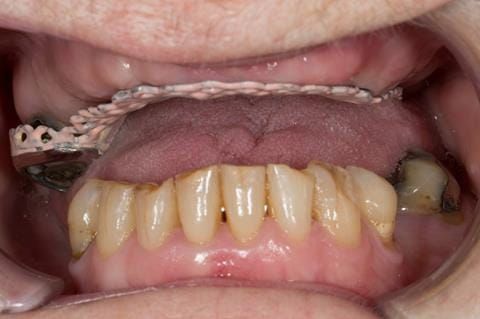

- Poorly fitting cobalt chromium based maxillary partial denture, which has been added to. This exhibited poor retention, stability and tissue fit (support). Unable to wear a new acrylic based denture.

- Eight mandibular anterior teeth worn incisal edges from now extracted maxillary anterior crowns. Gingivitis - owing to inadequate oral hygiene.

- Cobalt chromium reinforced gasket denture - using a Molloplast B "O" ring to retain and stabilise the denture. This was my professional preference as this was the least invasive and simplest solution to this dental problem. Should the UR7 require removal in the future - an artificial tooth could be added - resulting in a complete denture. The patient would have adapted to the denture fully by this stage and have good neuromuscular control of the prosthesis.

Following consultation and second discussion appointment the patient chose to have option 2 namely, a window denture - maxillary cobalt chromium based partial denture. The clinical situation and treatment process is shown in detail below with photographs. The patient was successfully rehabilitated with this and her quality of life considerably improved. The clinical work was provided by Finlay and the technical work by Rowan.